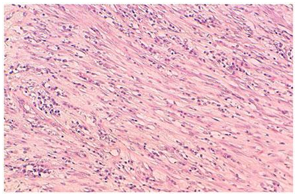

A 45year old male patient presented with a history of dyspnoea and cough since 8months. The patient was well built and nourished. His vitals were stable. Plain radiograph of chest, CT thorax was normal. Diagnostic bronchoscopic was done, the bronchial brushing was taken and was found to be positive for pulmonay tuberculosis (PTB). The patient was started on anti-tubercular therapy (ATT). He completed 6months of therapy and there was marginal reduction in the symptoms. A repeat CT thorax was done showing pleural thickening with hyperinflated left lung and bronchiectatic changes multiple patchy areas of consolidation in bilateral lungs. A CT guided biopsy was taken from the Left pleural thickening. The microscopy showed a mixed feature of spindle cells interlaced with plasma cells and lymphocytes. Immunohistochemistry (IHC) showed positivity for smooth muscle actin and vimentin and ki-67 index was 12%, the ALK was negative confirming the diagnosis of IMT. PET-CT was done which also confirmed the findings as in the CT thorax, with hyper-metabolic uptake in the left pleura and bilateral supraclavicular areas. The patient was continued on ATT till 9months, as well as started on pulsed dose steroid therapy starting dose at Oral prednisolone 30mg was started for 10days and tapered with 5mg decremental doses over a period of 4weeks (Figure 1–3).

Figure 1 PET-CT shows hypermetabolic activity in left lung.

The biopsy is necessary to confirm the diagnosis, which usually shows a combination of inflammatory cells and mesenchymal cells which mainly is the plasma cells, histiocytes, lymphocytes and spindle cells Pettinato et al.,5 has described IFT histologically to be a an inflammatory cells with proliferative myofibroblasts and fibroblasts, with IHC positive for vimentin and smooth muscle actin.6 The IMT can invade blood vessels but a rare occurrence, as it infiltrates the lung with the inflammatory cells, it is very difficult to differentiate as the normal lung architecture gets distorted. The imaging studies done at baseline was normal, but a repeat CT thorax was done showing pleural thickening with hyper inflated left lung and bronchiectatic changes multiple patchy areas of consolidation in bilateral lungs. PET-CT confirmed the findings with hyper-metabolic uptake in the bilateral supraclavicular areas. In our case the biopsy of the pleural thickening showed mixed areas of spindle cells interlaced with plasma cells and lymphocytes. IHC positive for smooth muscle actin, vimentin and ALK negative, confirming IMT.